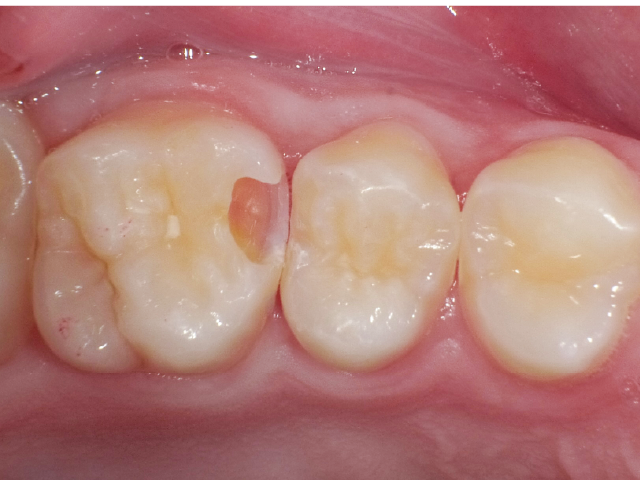

①窩洞形成段階(図1~7)

本症例では、ダイヤモンドの微粒子でコーティングされたエアースケーラーチップを窩洞形態の仕上げに使用。隣在歯の誤切削を防止し、エナメル質の切削断面を歯肉側窩縁までなめらかになるよう仕上げました。